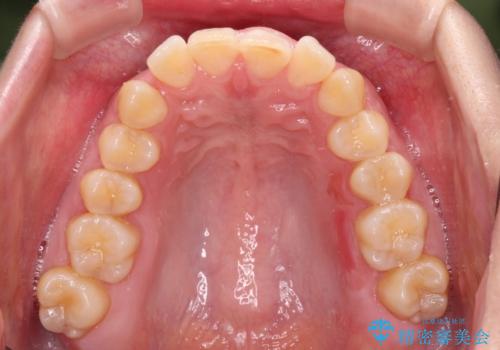

- 上顎前歯の前方に傾斜した咬み合わせを気にして来院された患者様です。

奥歯の咬み合わせを見ると、上顎が下顎に対して相対的に前方にありました。

深い咬み合わせを改善するためには、上顎臼歯を後方に移動させつつ、下顎の小臼歯を直立させる必要があります。

インビザライン単体で対応ることも検討できますが、達成する可能性が低いため、カリエールディスタライザーという補助装置を併用して、より確実性を上げることとしました。

奥歯の咬み合わせと深い咬み合わせを改善した後、インビザラインで歯列を整えることとしました。

カリエールディスタライザーや部分的なワイヤー矯正を併用したことで、確実かつ短期間で治療を終えることができました。